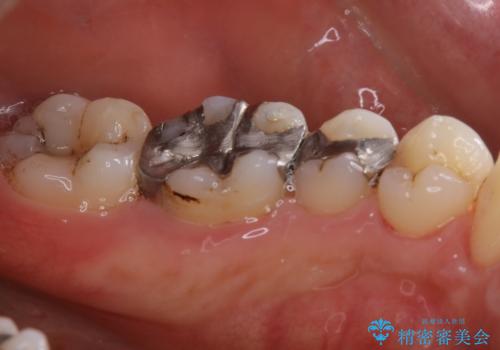

歯の表面に、茶色く色が残っている所がありますが、これは詰め物の変色の所と、虫歯になっている所です。以前に、CR(コンポジットレジン)による虫歯治療がされています。

CRは経年的劣化や、着色してしまうことがあります。PMTCでクリーニングを行うと、古いCRが目立つことがあるため、気になる際は詰め替えを行います。

茶色くなっている部分が、着色なのか、劣化なのか、虫歯によるものなのかは判別が難しいことがあります。そのため、定期的にPMTCを行うことで状態の確認が的確に行えます。